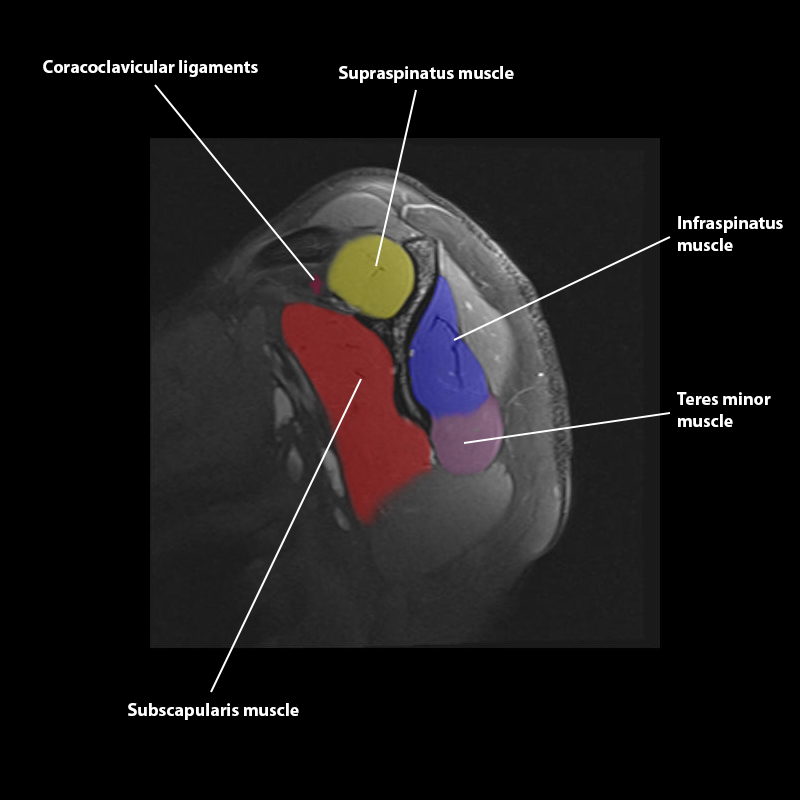

Shoulder MRI Anatomy